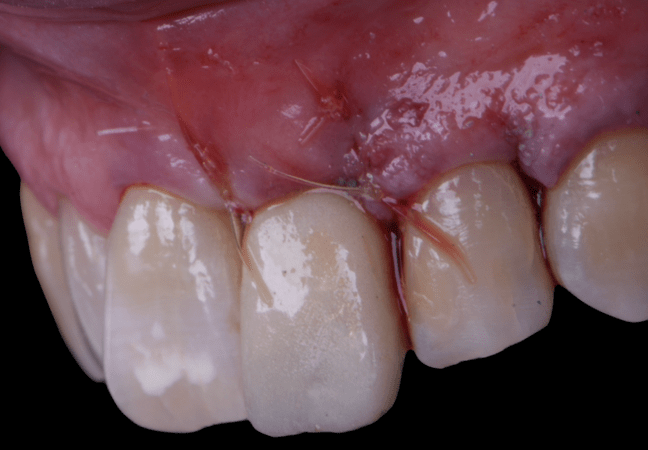

The surgical protocol began with the atraumatic extraction of tooth 1.1 to preserve as much of the alveolar socket as possible. Immediately following extraction, an N1 implant was placed into the socket using a guided surgical approach to ensure ideal three-dimensional positioning. The “one abutment one time” technique was applied to minimize soft tissue manipulation during the healing phase, which is particularly important in esthetic areas.

Given the significant buccal defect, guided bone regeneration (GBR) was performed simultaneously. A mixture of autologous bone and creos™ xenogain™ was applied to the defect and covered with a resorbable creos™ membrane to restore ridge width and support the buccal contour. In addition, a connective tissue graft was harvested and placed in the vestibular region to increase the thickness of keratinized mucosa. This combined approach addressed both hard and soft tissue deficiencies, providing the biological foundation for a stable and esthetic outcome.

On the same day as the surgery, an immediate-load provisional crown was delivered. This restoration was fabricated in acrylic resin and screw-retained on the implant, following the “one abutment one time” principle. The provisional crown was carefully adjusted to avoid occlusal loading while supporting the peri-implant soft tissue architecture during the healing phase.